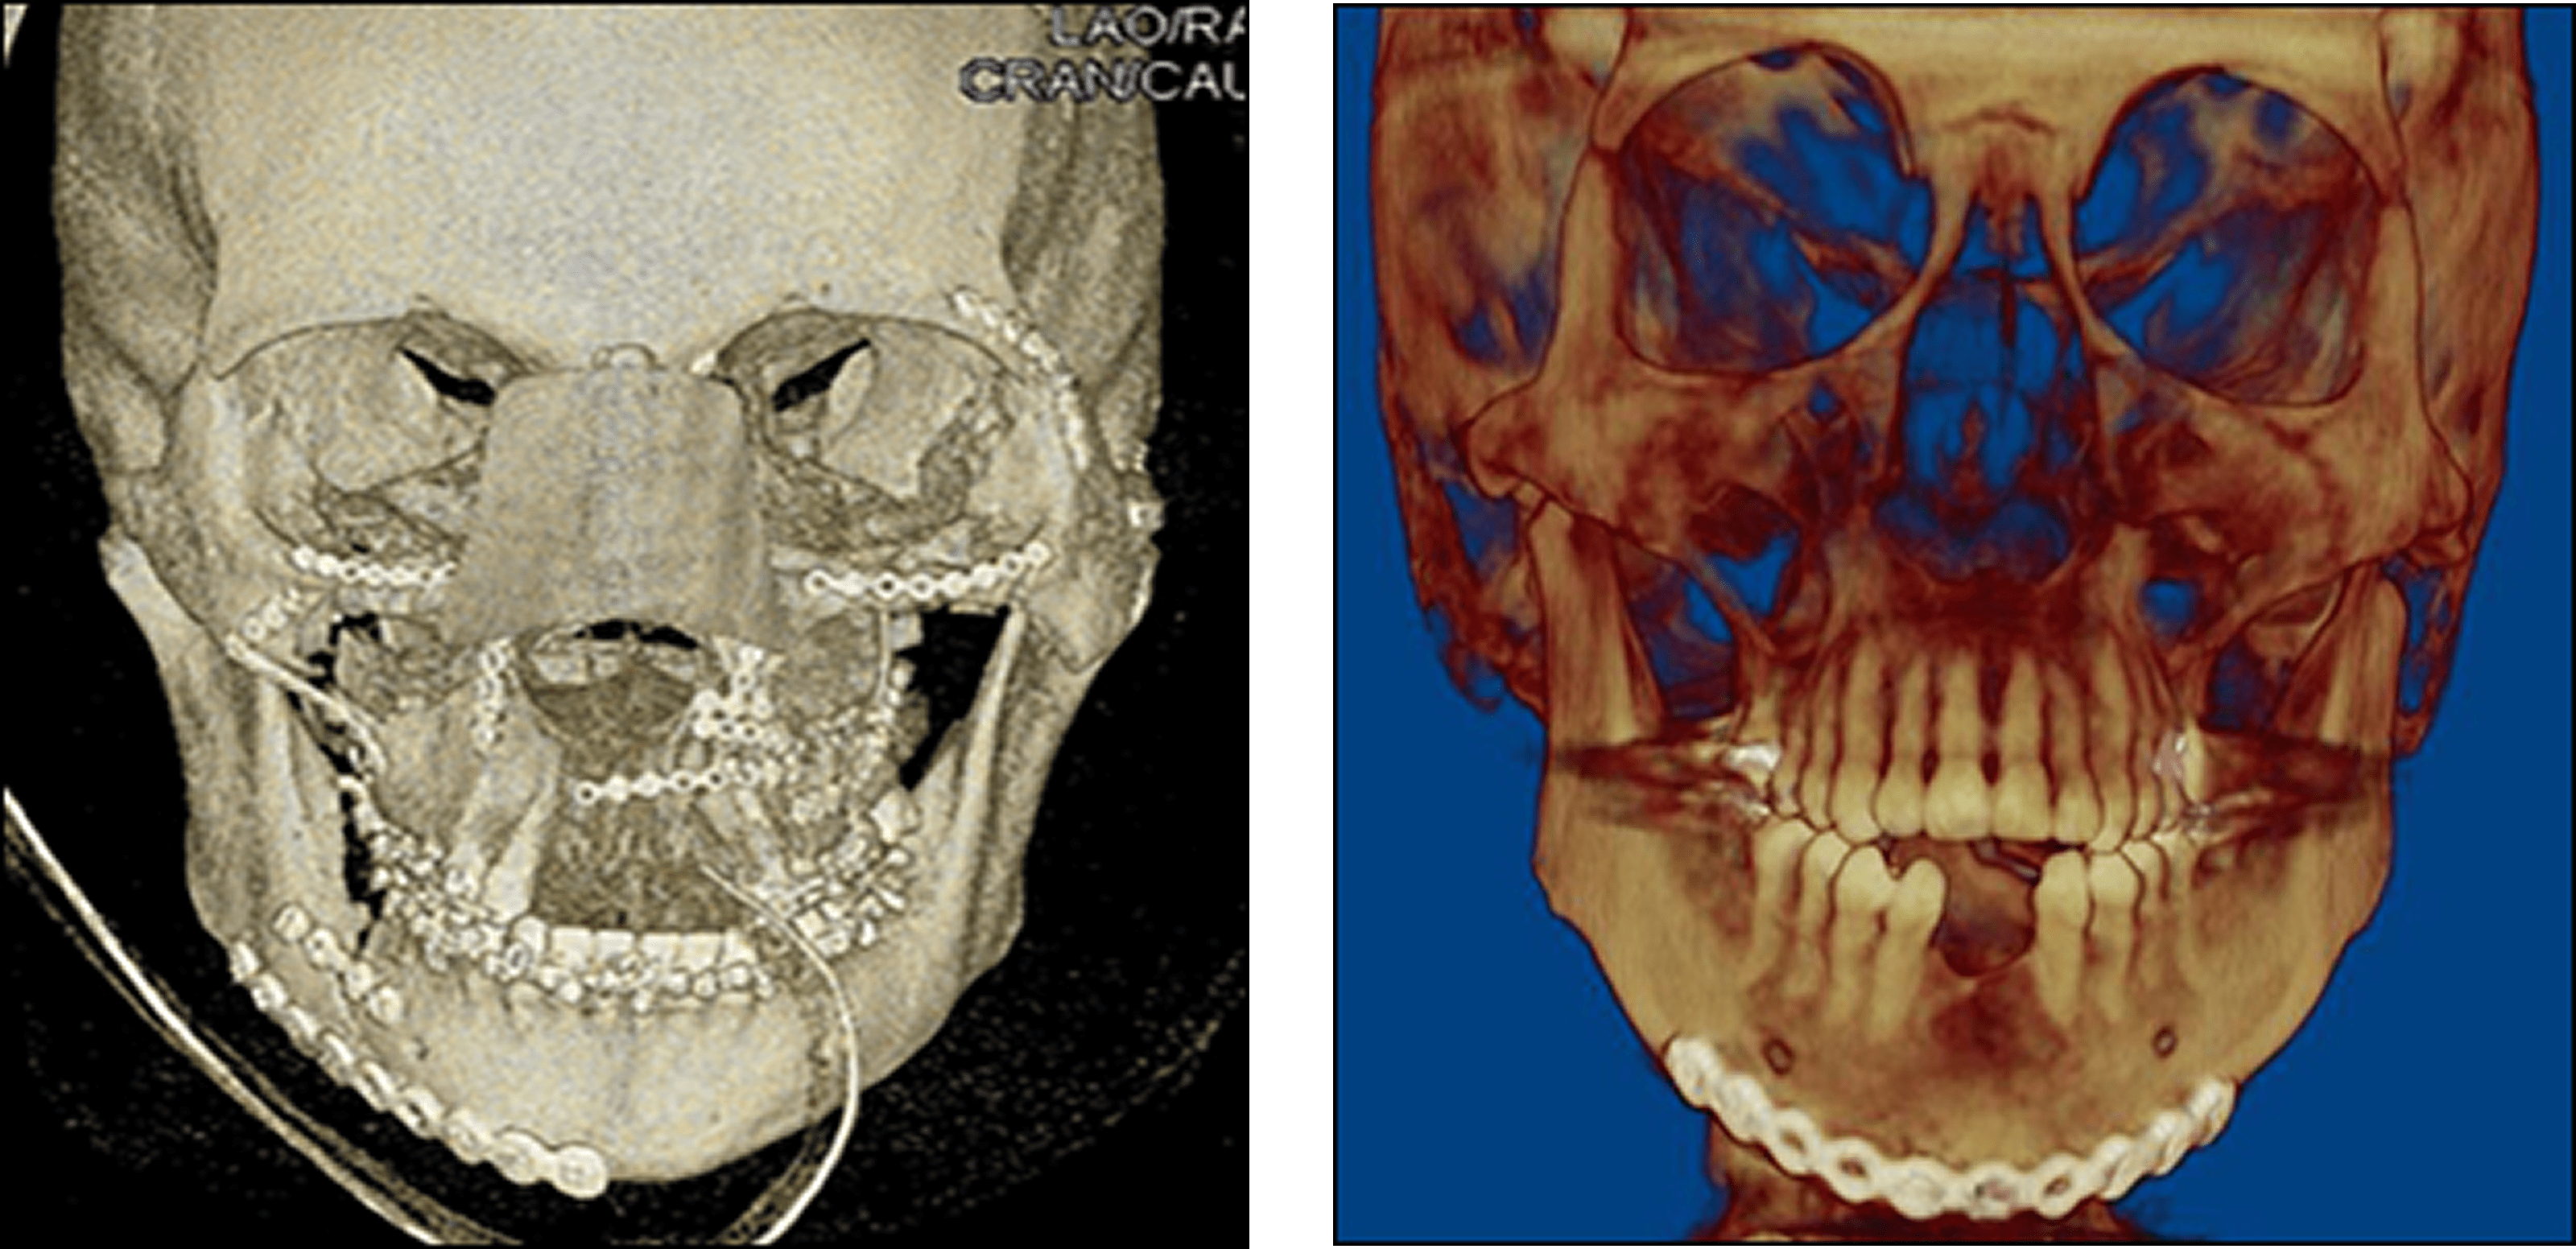

Facial Fractures

There are a number of possible causes of facial trauma such as motor vehicle accidents, accidental falls, sports injuries, interpersonal violence, and work-related injuries. Types of facial injuries can range from injuries of teeth to extremely severe injuries of the skin and bones of the face (cheek, nose, orbit, upper and lower jaw). Injuries to the face, by their very nature, impart a high degree of emotional, as well as physical trauma to patients. The science and art of treating these injuries requires special training involving a “hands on” experience and an understanding of how the treatment provided will influence the patient’s long term function and appearance.

Facial Feature

SOFT TISSUE INJURIES

When facial lacerations occur they are repaired by suturing providing the best cosmetic result possible, care is taken to inspect for and treat injuries to structures such as facial nerves, salivary glands, salivary ducts (or outflow channels of saliva) and blood vessels.

Injuries of the facial bones

Fractures of the bones of the face are treated in a manner similar to the fractures in other parts of the body. The specific form of treatment is determined by various factors, which include the location of the fracture, the severity of the fracture, the age, and general health of the patient. When an arm or a leg is fractured, a cast is often applied to stabilize the bone to allow for proper healing. Since a cast cannot be placed on the face, other means have been developed to stabilize facial fractures. One of these options involves wiring the jaws together for certain fractures of the upper and/or lower jaw.

Certain other types of fractures of the upper and lower jaws, cheek bone and frontal bone are best treated and stabilized by the surgical placement of small plates and screws at the involved site. This technique is called “rigid fixation” of a fracture. The relatively recent development and use of rigid fixation has profoundly improved the recovery period for many patients, allowing them to return to normal function more quickly. The incisions are designed to be small, placed intraorally and if it is necessary to go through the skin they are hidden to avoid visible scars.

Fractures of the nose are treated with reduction and stabilization with intranasal packing (2-3 days) and external splint (7-10 days). Fractures of multiple bones of the face are called panfacial fractures, the repair of these fractures is more difficult and several hours of surgery are needed to obtain a good result. In some cases additional procedures have to be done to reconstruct the facial structures.

Injuries to the teeth and surrounding dental structures

These types of injuries are treated by one of a number of forms of splinting (stabilizing by wiring or bonding teeth together). If a tooth is knocked out, it should be placed in salt water or milk. The sooner the tooth is re–inserted into the dental socket, the better chance it will survive.

The proper treatment of facial injuries is now the realm of specialists who are well versed in emergency care, acute treatment, long-term reconstruction, and rehabilitation of the patient.